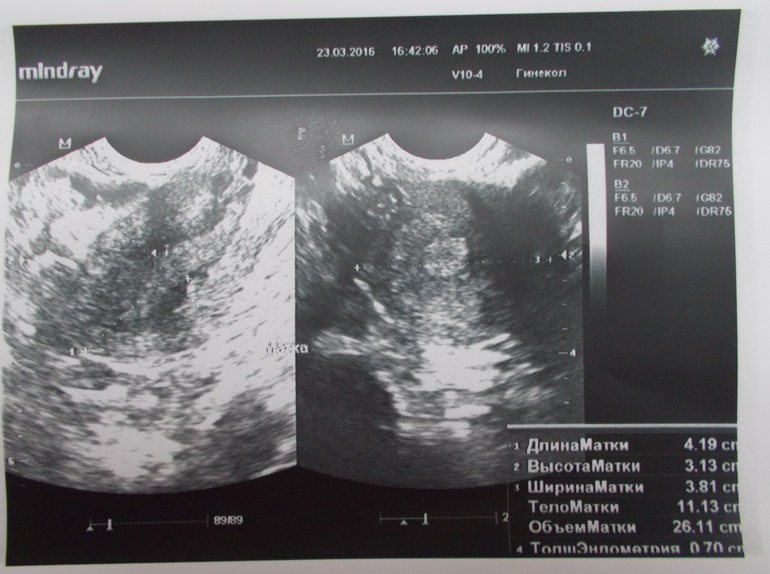

МАТКА расположена кпереди, хотя нашла старое УЗИ, там написано кзади, размеры нормальные, контуры ровные, эхоструктура однородная,образований нет

Эндометрий 7мм

ЗАКЛЮЧЕНИЕ Ставят мультифолликулярные яичники!!!узистка долго сомневалась писать такое заключение или нет, но всё-таки написала....((( ещё сказала, что в шейке матки есть малюсенькие кисты!других паталогий не выявлено!

Снимки прилагаю.

Если есть комментарии по поводу снимков, пишите, потому что я в них вообще ничего не понимаю!